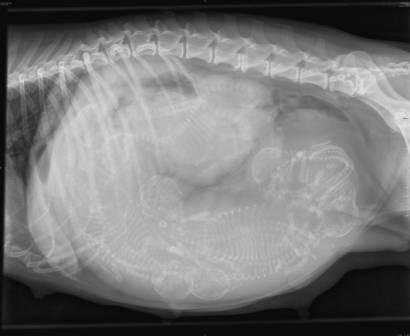

Här är röntgenbilden på Flingan som togs innan snittet, längst till höger ser ni valpen som låg med ryggen mot passagen och blockerade.

När vi kom in så togs en röntgenplåt och konstaterade att en valp låg som en ostkrok i vägen så ingen kunde komma ut. Snabbt som attan sövdes Flingan och Ritva snittade henne.